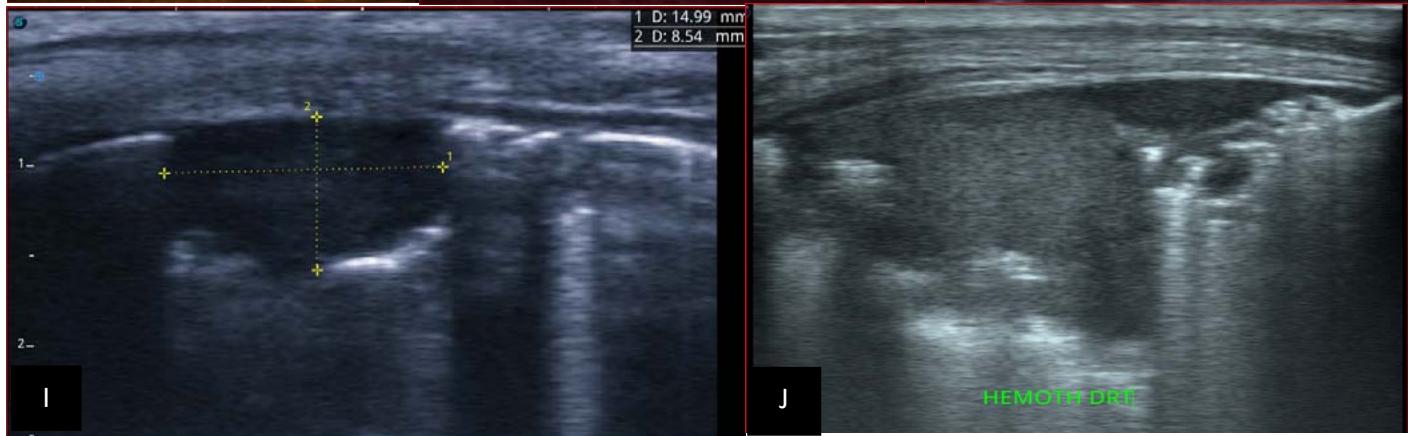

Figure 5: Abdominopelvic ultrasound control after 6 courses of chemotherapy in the same 3 year old patient with a ruptured left renal nephroblastoma; Images A, F, G, and H: show regression of the solid, endo and exo renal, left nephroblastoma mass treated with 6 courses of chemotherapy (current volume 430 ml vs) Images: B, C, and: show persistence of thrombotic permeation pan vena cava and ipsilateral renal. Image E: shows a volumetric regression of the intra-lesional hematic collection, at the tumor rupture estimated at 34.49 ml VS, Image I: represents the right kidney in B mode which is of normal echoculture. Source: Dr. Frederick Tshibasu Tshienda database.